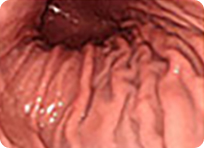

매우 작고 미세한 변화만을 보이는 조기위암들

풍부한 내시경 경험을 가진 의료진이 최신의 내시경 기계를 이용하여 세심한 관찰을 해야 위와 같은 매우 작은 조직 위암을 놓치지 않고 진단할 수 있습니다.

조기 위암이 진행이 되어 진행성 위암이 되어야만 비로소 구토, 복통, 체중 감소, 소화불량, 토혈 등 여러 가지 증상이 나타나게 됩니다.

조기 위암과 같이 위암을 초기에 발견할 경우 완치가 가능하나 진행성 위암과 같이 암이 많이 진행되어 발견될 경우는 현대 의학으로도 치료할 수 없습니다.

진행성 위암